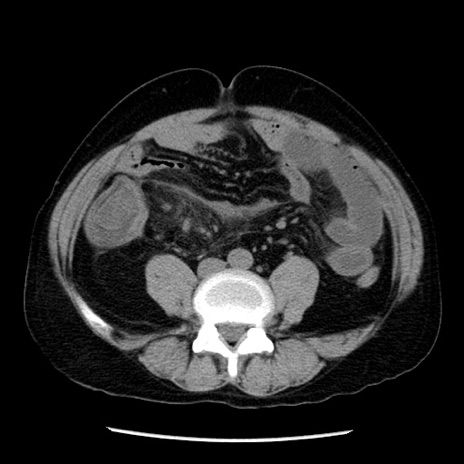

症例29(横断像)

【症例】40歳代男性

【現病歴】2日前から胃痛あり。徐々に周期的な激痛に変化した。本日になっても激痛があるため受診。

【身体所見】意識清明、BT 38-39℃台あり、腹部:膨満、やや硬、右下腹部に圧痛あり。

【データ】WBC 8500、CRP 23.26